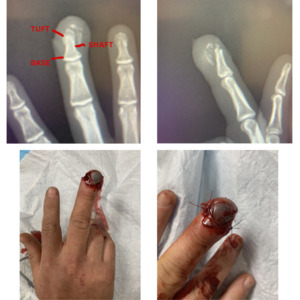

The force applied by the nail gun had caused the bone to fragment from the tuft down to the top of the shaft, indicative of a crush injury. The nail was fragmented as well as significant damage to the flesh and nerves of the fingertip, the nail bed however was intact.

Diagnostic imaging revealed a comminuted fracture of the distal phalanx (tuft fracture). Interrupted absorbable sutures were then placed on the left and right side of the finger to support healing, and the fingernail was not removed given its role as a biologic dressing [Figure 1]. Given the bone fragments were contained and the fracture was extra-articular, treatment could be fully provided within the ER and the patient was discharged.